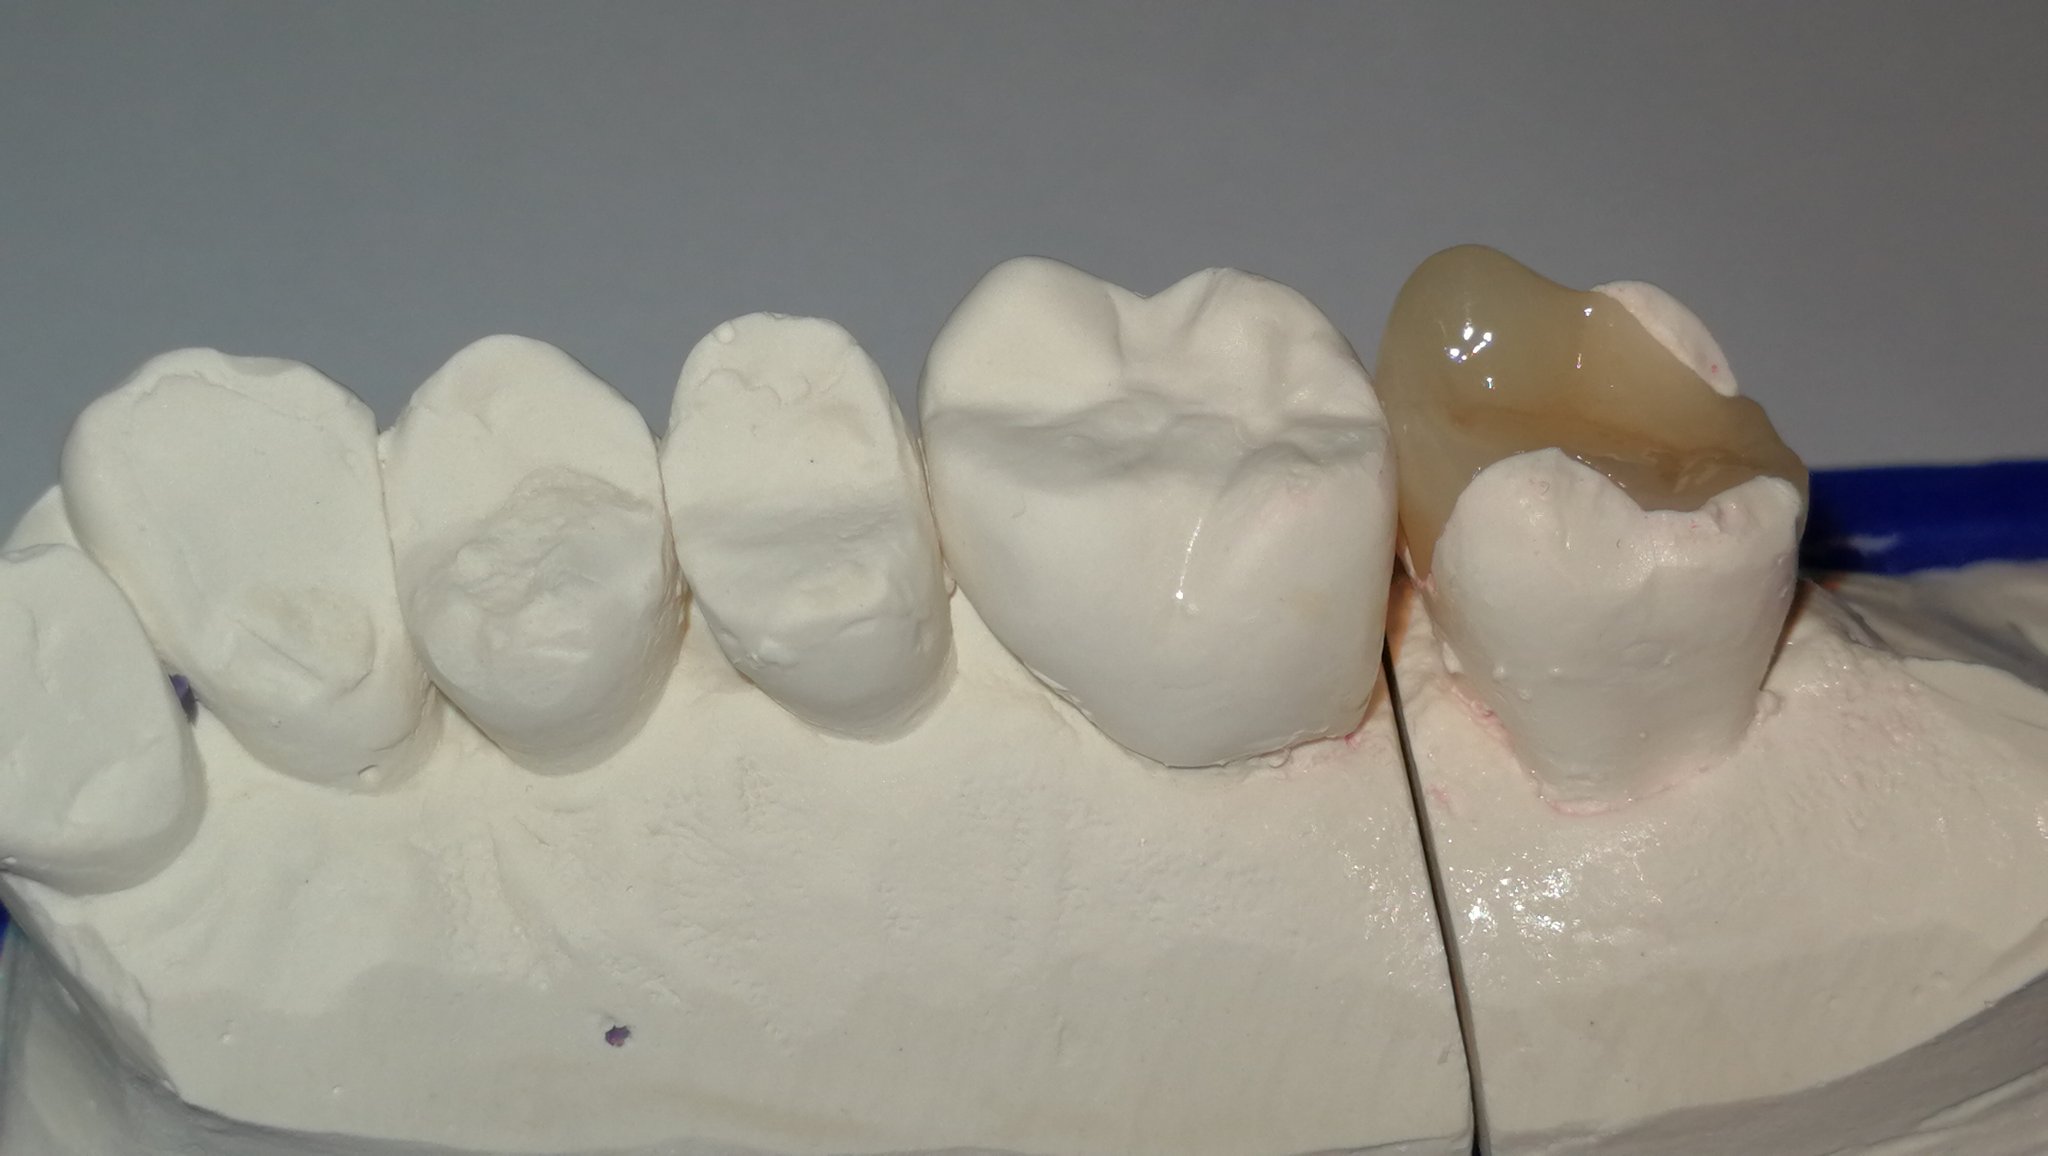

Grössere Defekte der Zahnhartsubstanz werden idealerweise in Keramik restauriert. Meist wird das Werkstück von einer Fräsmaschine (CAD; computer-aided

design) aus einem Keramikblock gefräst.

So können grosse Füllungen (Inlay, Onlay, Overlay), Veneers (Verblendschalen) mit höchster Passgenauigkeit und Stabilität hergestellt werden. Nach dem Fräsen wird das Keramikwerkstück mit einem Kompositzement in / auf den Zahn geklebt (einzementiert).